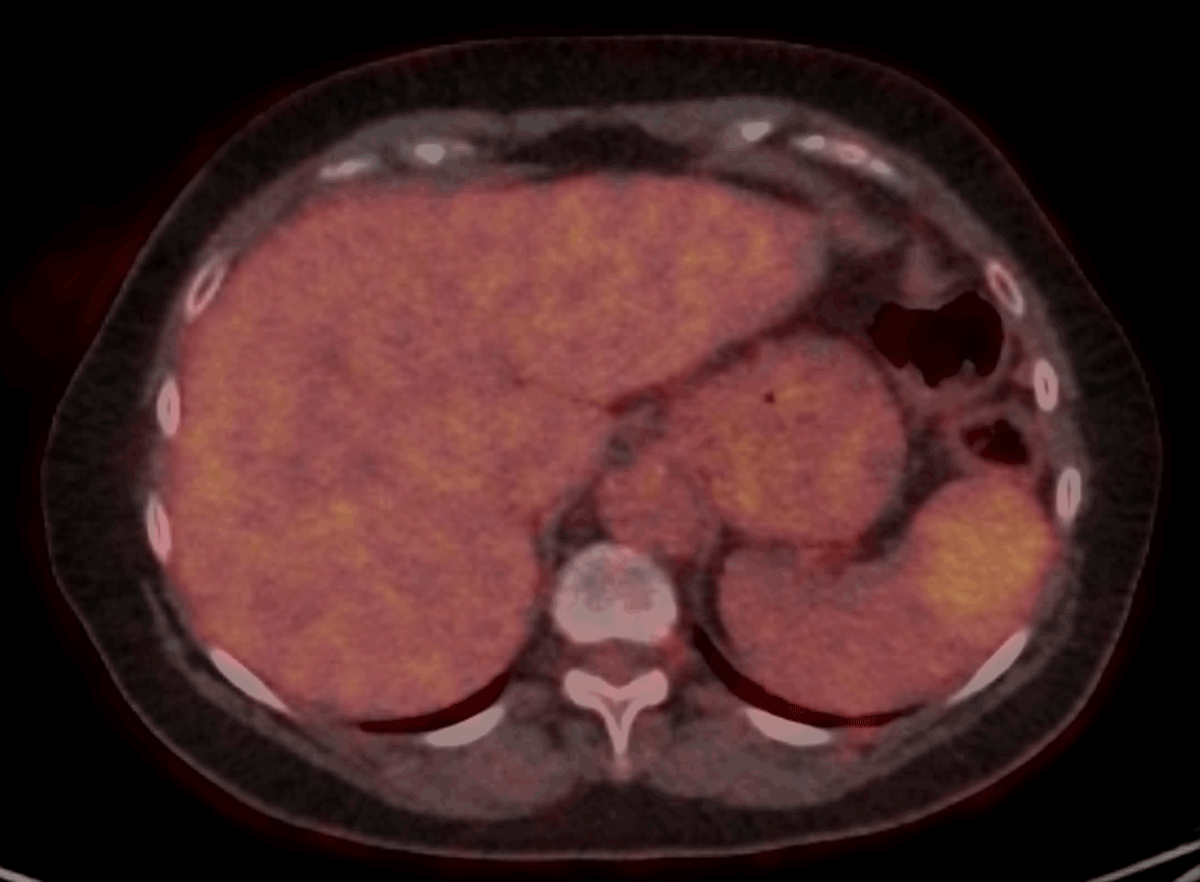

Figure 3

Axial Fluoro-deoxyglucose-Positron Emission Tomography shows a moderate uptake in the splenic lesion. Extra-splenic lesions were absent.